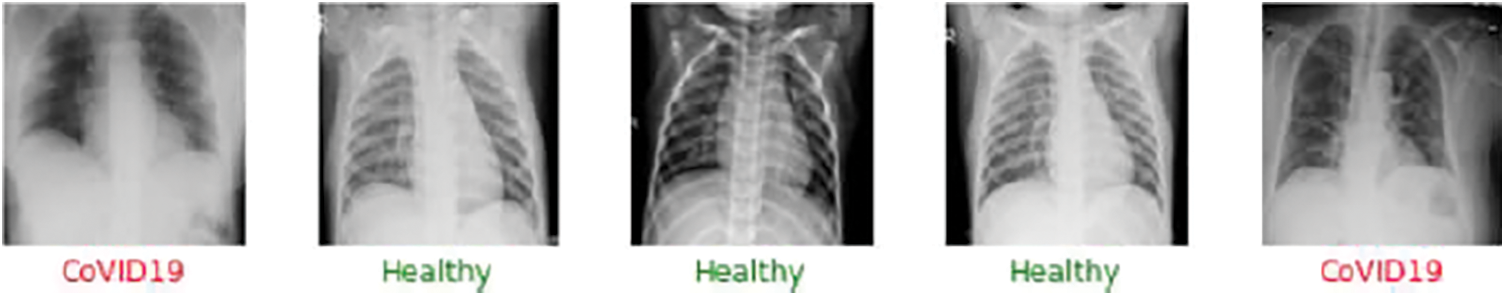

In order to continue with the model analysis, we will use two alternative categorization methods. In the first scenario, we will see if one can find out how the model can tell the difference between the Healthy and COVID-19 cases. The training and testing samples will be divided by 75% and 25% in this binary classification model, respectively. Next, we will run the entire Google Colab with the GPU instance to validate the model. The first data set sample is presented in Fig. 7.

Figure 7: Sample output of the model for the binary classification between the healthy and the COVID-19 cases. The green color in the medical terminology determines the safe